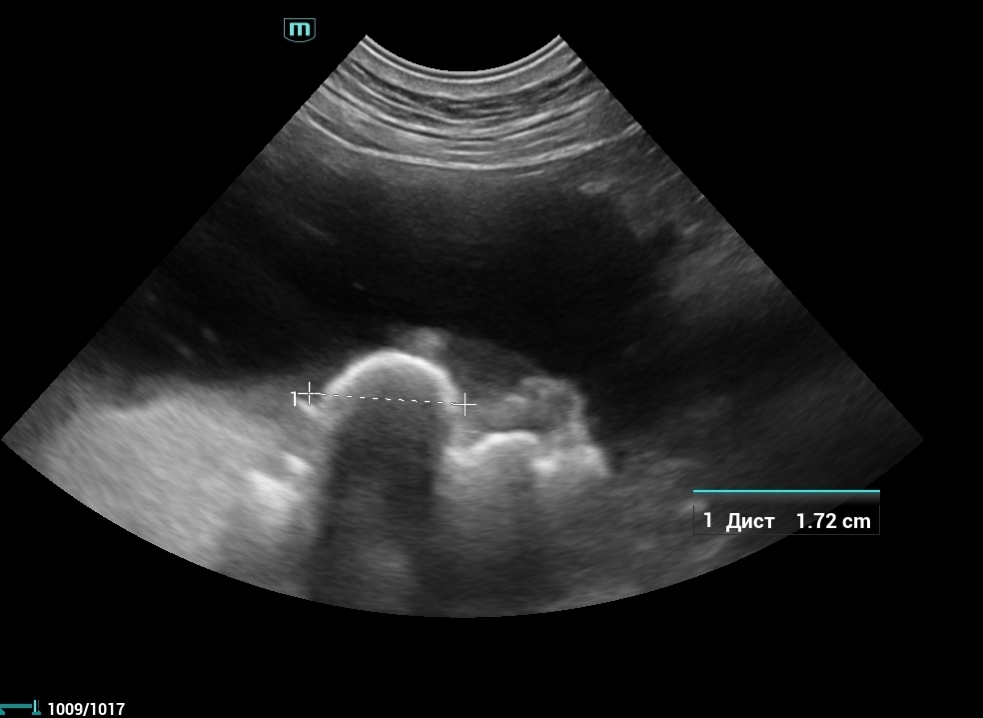

Драгоценный улов: как мы достали камни из мочевого пузыря собаки без операции

Мы достали огромное количество камней из мочевого пузыря собаки БЕЗ ОПЕРАЦИИ 😱

Как такое возможно ? Только благодаря литотриптору

Литотриптор — это современное оборудование, которое используется для безоперационного разрушения камней в мочевом пузыре и почках у наших пушистиков. 🐶🐱 🔍